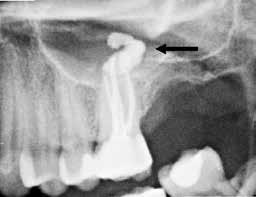

Fig. 1. A. Udsnit af panoramaoptagelse viser Ca(OH)2 uden for foramen apicale i en overkæbemolar og i sinus maxillaris (pil). B. Periapikal optagelse viser Ca(OH)2 uden for foramen apicale (pil) i en central incisiv. Tilfældet krævede kirurgisk indgreb.

Fig. 1 A. An orthopantomography section showing Ca(OH)2 beyond the apical foramen of maxillary first into the maxillary sinus (arrow) and (B) a periapical radiograph with Ca(OH)2 extrusion beyond the apical foramen (arrow) of a central incisor which required surgical intervention.

Ved mistanke om malpraksis vurderer man behandlerens handlinger i alle stadier i relation til opgavens kompleksitet og tager stilling til, om disse lever op til normen for almindelig anerkendt faglig standard. De mest omfattende skadevirkninger ses i forbindelse med anvendelse af endodontiske skyllevæsker og andre medikamenter, fx ulykker med natriumhypoklorit eller skader på nervevæv eller i sinus som følge af udpresning af calciumhydroxid igennem foramen apicale (Fig. 1A og B) (5,6). Sådanne uheld vurderes ofte til at være undgåelige, idet tandlægen ikke har levet op til normal faglig standard. Frygt for at begå procedurefejl eller andre utilsigtede hændelser bør dog ikke få klinikeren til helt at afstå fra at foretage endodontiske behandlinger (7).